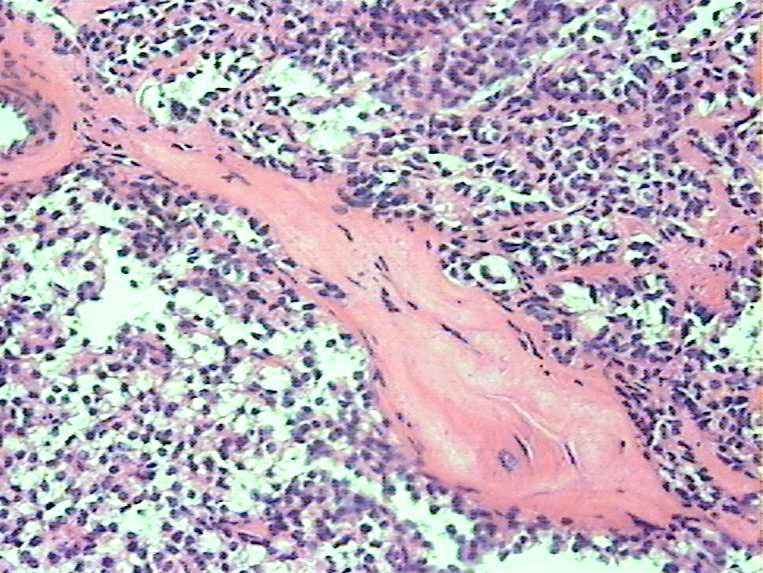

胰腺肿物 大体:灰白色肿物一枚大小:3*2*2cm,切面实性,质中。女,52

胰腺实性-假乳头状瘤

会诊实性假乳头状瘤